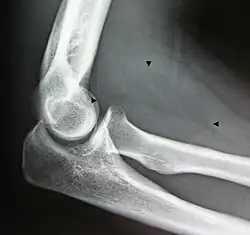

Bone formation may be seen in both lipomas[26] and liposarcomas (a well-differentiated one pictured).

- Resection of an intermuscular lipoma in the elbow region

-

Intraoperative photo -

Operating field after removal of the lipoma: Arrow marks the median nerve that was compressed by the lipoma. -

The resected lipoma

(8 cm × 6 cm × 3 cm)